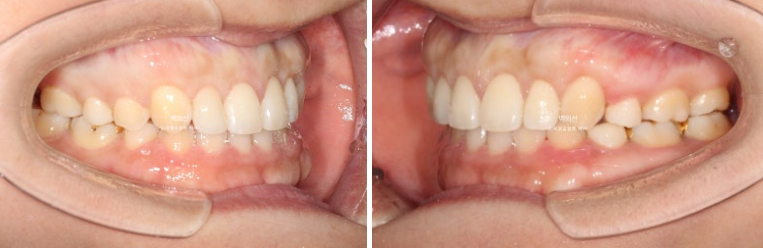

23.07~25.07

비대칭으로 인해 어긋났던 중심선이 맞아졌습니다.

교정만으로 턱뼈의 비대칭을 바꿀 순 없지만 최소한 치아중심선은 정확히 맞춰줄 수 있습니다.

어금니 교합관계는 좌우 모두 1급 입니다.